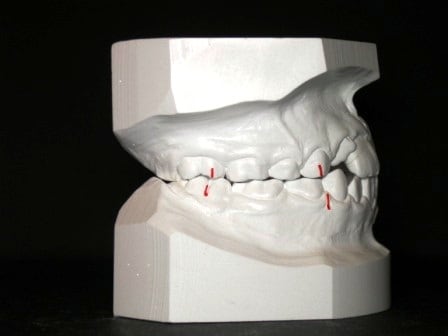

il s’agit ici, d’une Cl.II. 2. division 2, (avec les latérales qui rentrent). avec un seul arc, je m’appuie sur le blocage des incisives latérales pour déverrouiller en Post. et lancer l’expansion

un double arc, qui serait ligaturé dans la gorge de 12/22 serait trop puissant, réalignerait en premier les incisives Lat. en créant une version Ant. indésirable des Inc. Centrales.

Sur les photos, il me semble voir une classe II molaires droite, une classe I( voir III molaires gauche),et une forte déviation des milieux incisifs. Je ne vois pas de classe II/2. Si ton diagnostic de départ est érroné, tu n'arriveras à aucun résultat satisfaisant...sauf à aligner les quatre incisives :-(

je suis d'acord avec toi Bjc, la Cl II2 est de temps en temps en pseudo ClI molaire avec une supra et des latérales en vestibuloversion par rapport aux centrales...mais là pour moi c'est pas du tout une Cl II 2

tu appellerai cette classe comment ?

D.D.M. tendance Cl. II.

voici la mécanique mise en place pour ce cas et comment j’utilise (en friction faible, forces faibles) le fait que les Inc. Lat. soient bloquées en lingual pour le redressement des 3/4/5 tout en évitant la pro-version des Inc. centrales qui est Tjs. longue à rattraper et peut occasionner des rhizalyses

Modèles de départ@+ Bjc.